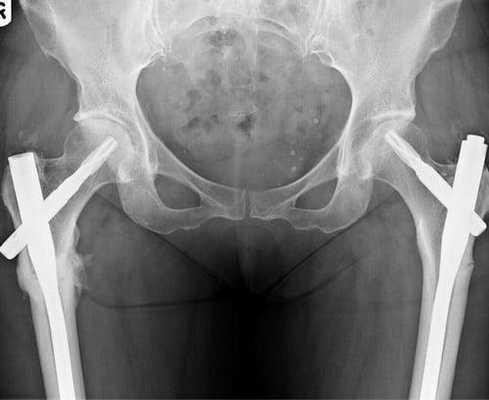

Вмешательство выполняется для уравнивания длин нижних конечностей, чтобы вернуть человеку нормальные способности к передвижению, без признаков хромоты. Наиболее простым способом, чтобы удлинить одну из ног, признается остеотомия по принципу косого разрезания кости. Для компенсации имеющегося укорочения иногда рекомендуется процедура, предусматривающая ступенеобразный распил диафиза бедренной кости, но она технически намного сложнее. Удлиняющая операция всегда сочетается с компрессионно-дистракционным остеосинтезом (установкой чрескостных аппаратов вытяжения на конечность).

Наружный остеосинтез. Метод хирургической терапии, основанный на репозиции отломков дистракционно-компрессионными аппаратами наружной фиксации.

Востребованной методикой чрескостного остеосинтеза является закрепление на внешних опорах комплекта Илизарова. Ранее было широко распространено хирургическое вмешательство по Веберу — сращение перелома с помощью металлических спиц и проволоки. Сейчас эта методика остеосинтеза считается устаревшей.